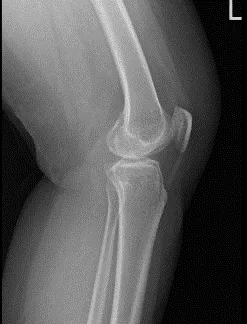

A 66-year-old patient was in our office with complaints regarding left knee pain. She has been experiencing this pain for a month. She denies any injury to the knee. She went to her PCP who recommended x ray showing bone on bone. She presented an Xray result that showed no significant degenerative changes.

There are no acute fractures. She also presented an MRI results that showed trace joint effusion. Tiny popliteal cyst. Minimal lateral patellar shift. Degenerative medial and lateral meniscus tears as detailed above. Minimal osteoarthritis in the medial and lateral joint compartment of the left knee.

Left Knee X-ray AP and Lateral with Oblique 3 views